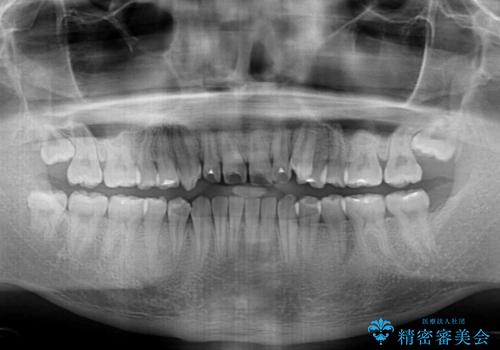

- 八重歯と前歯の隙間を気にして来院された患者様です。

八重歯の改善のため、奥歯を後方に移動させていくこととし、患者様と相談の上、ワイヤー装置にて矯正治療を行うこととしました。

上顎前歯正中の隙間は、舌突出癖によるものと考えられ、舌のトレーニングによる悪習癖改善が必須であるため、徹底するよう指導してから治療を開始することとしました。

舌突出癖が改善されず、なかなか正中の隙間や上下の前歯が接触しなかったために治療が長期化してしまいました。

また、治療期間中のプラークコントロールが悪く、ブラッシング指導も奏功しなかったため、装置の周りが脱灰した状態(初期むし歯)となってしまいました。